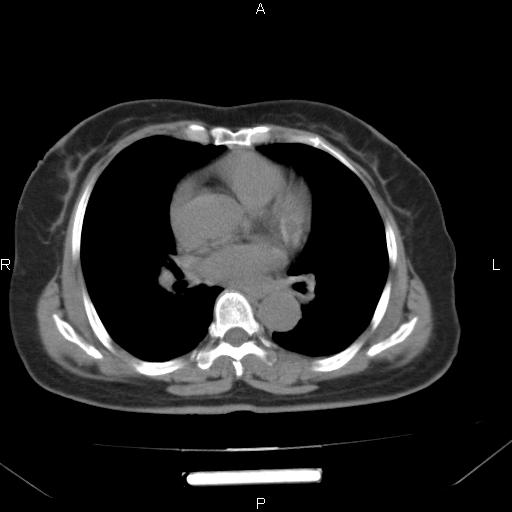

胸腺瘤

女、63Y 双眼睑下垂,早轻晚重。 胸腺瘤???

结果胸腺瘤